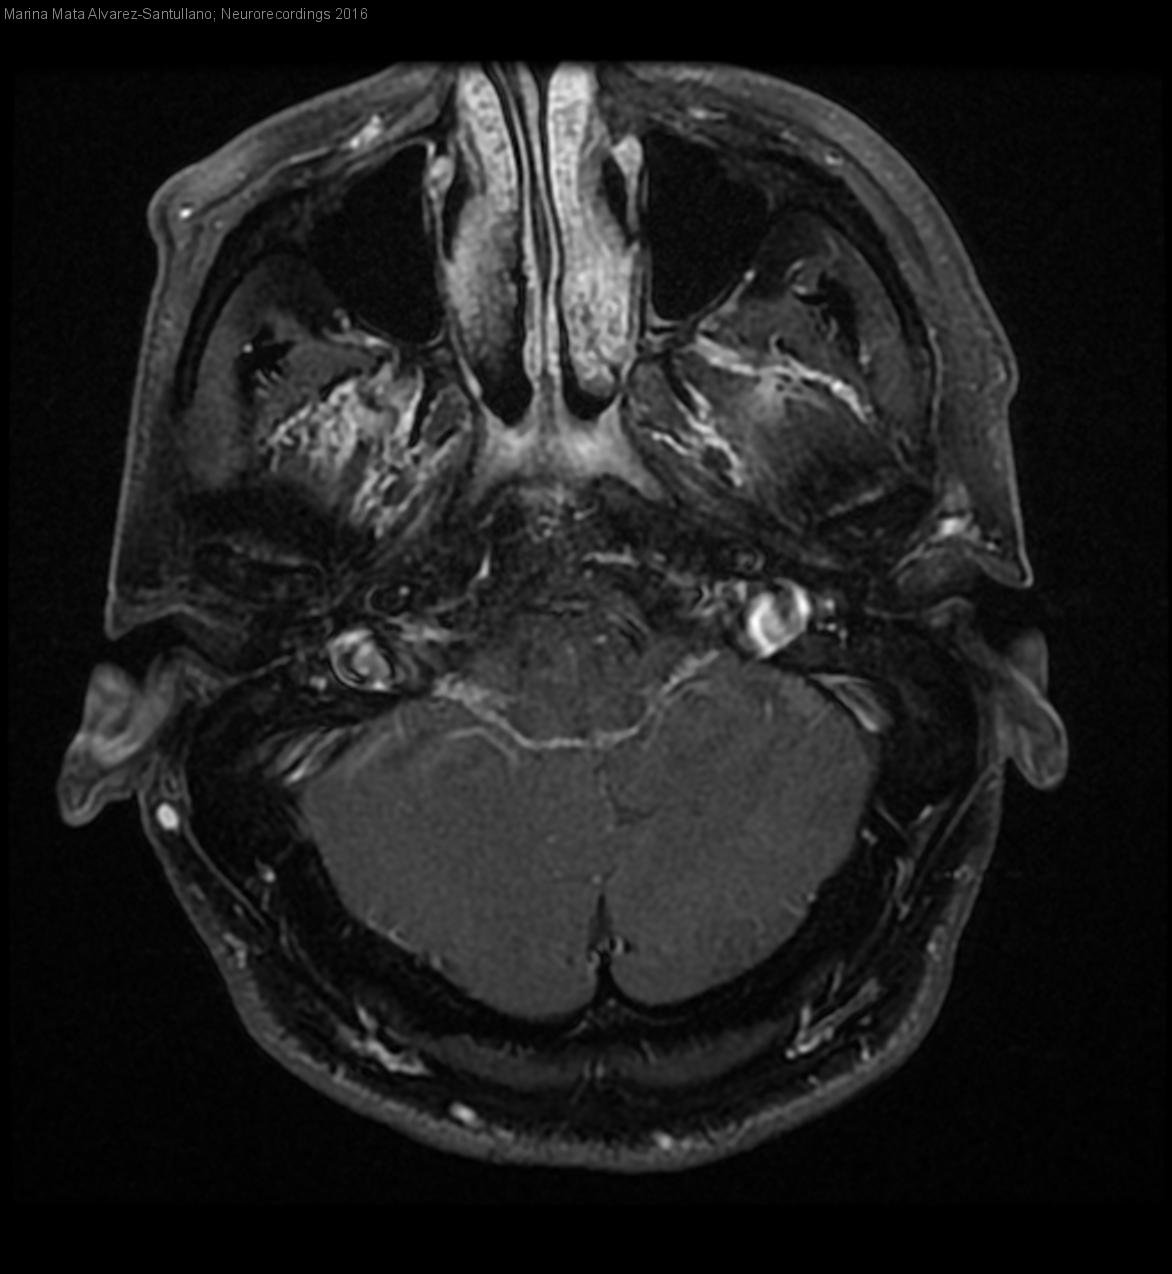

Parálisis facial periférica por neuritis del VII nervio craneal con afectación protuberancial

Diagnóstico final: Neuritis del VII nervio craneal

Acude a Urgencias el 1 de julio de 2013 por cuadro de paralisis facial periférica derecha, precedida dos dias antes de dolor retroauricular. Se inició tratamiento con corticoides. Exploración OD: perforacion reepitelizada con membrana muy...